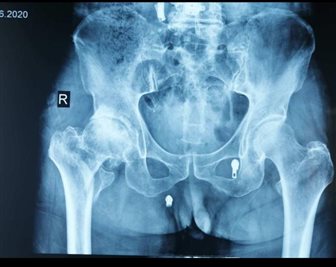

近年来,骨外科开展了我院的多项骨科首例手术,熟练开展髋关节置换手术、老年患者髋部骨折的髓内钉内固定术、胸腰椎体骨质疏松骨折的椎体成型手术、胸腰椎骨折微创内固定术等;在骨科多发伤、复杂骨折、老年患者骨质疏松治疗方面积累了丰富的经验。目前,骨外科成功完成胸腰椎椎体成型术年手术量70余例,可同时做三个椎体成型术,多数患者年龄在70岁以上,80岁以上患者占三分之一,所有患者术后腰背部疼痛均明显缓解。髋关节置换术已成为科室常规手术,髋关节置换年手术量50余例,膝关节置换、关节镜手术近年来手术患者均明显增加。科室能开展所有四肢骨折的手术治疗,年手术量达200余例。

近年来由于老龄患者明显增加,苏纯柱主任针对老年骨质疏松做了大量的工作,对于老龄骨质疏松骨折立足于防治结合,强调对于骨质疏松的早期干预治疗,指导患者规律治疗骨质疏松症。科室治疗的髋关节置换手术患者年龄最大92岁,术后一周患者自己步行出院。腰椎成型术最大年龄患者94岁,患者术后腰痛明显缓解,第二天即可下床活动。老年骨质疏松骨折的快速康复赢得了患者及家属的高度赞扬,提高了患者生活质量,所开展手术取得了患者的广泛认可,赢得了社会赞誉。

从事外科工作20余年、先后在山东省立医院、齐鲁医院、山东省千佛山医院进修学习,在临床工作中积累了丰富的经验。擅长骨科、普外科手术精细化、微创化操作,熟练开展四肢骨折、脊柱骨折的手术治疗,在全院率先开展了下肢骨折的MIPPO治疗、股骨近端髓内钉的闭合复位治疗、老年患者的骨质疏松骨折的椎体成形术、全髋关节置换术,熟练开展普外科常见病、多发病的手术治疗,广泛开展了腹腔镜下的阑尾切除术、腹股沟疝修补术、胆囊切除术、结直肠肿瘤切除术。在颈腰部、软组织疼痛治疗方面有深入研究,开展了肌肉软组织疼痛、膝关节疼痛的PRP治疗、针刀治疗、封闭注射等疗法,大大缓解了患者疼痛。在临床工作中坚守“医者仁心、患者至上”的宗旨、带领科室主动学习新技术、新方法,提高医疗技术、提高为患者服务的能力,开展了多例高难度复杂手术,为南部山区广大患者解除病痛,多次受到患者高度赞扬,赢得了患者的信任。